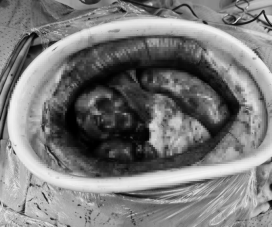

不久前,60岁的熏先生(化名)因腹部剧烈疼痛前往滨医烟台附院就诊,查体时见全腹部膨隆,同时伴有腹膜炎、感染性休克表现。李雷副主任医师结合影像分析并综合研判患者病情后考虑腹茧症并肠坏死,在与患者及家属进行充分沟通后迅速制定了手术治疗方案。术中,当打开腹腔之后,在场的手术医生全都倒吸一口凉气,因为映入眼帘的是个占据整个腹腔的肉球,表面像套了一身紧身衣,肉眼很难分辨肠管、血管等组织的走向。“腹茧症”,一种临床极罕见、病因不明的特殊类型肠梗阻,被称为“肠梗阻中的天花板”,同时也是所有普外科医生的“噩梦”。术中肠粘连非常严重、致密,伴有肠管坏死,腹腔污染严重。这让手术难度陡然提升。凭借丰富的经验,陈军主任带领团队细致操作,一点点将纤维包膜整个剥离,使肠管恢复至正常的解剖位置,并顺利切除了梗阻、坏死的肠管,重建消化系统,使整个肠道重获蠕动的能力。手术难度非常大,历时5小时,最终顺利完成手术。